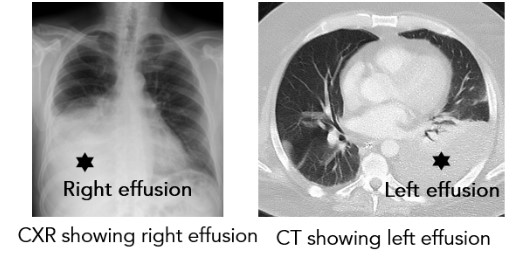

What Tests Can Help Diagnose Pleural Effusion?

- Ultrasound

- Chest X-ray (CXR)

- Computed Tomography (CT) scan – chest